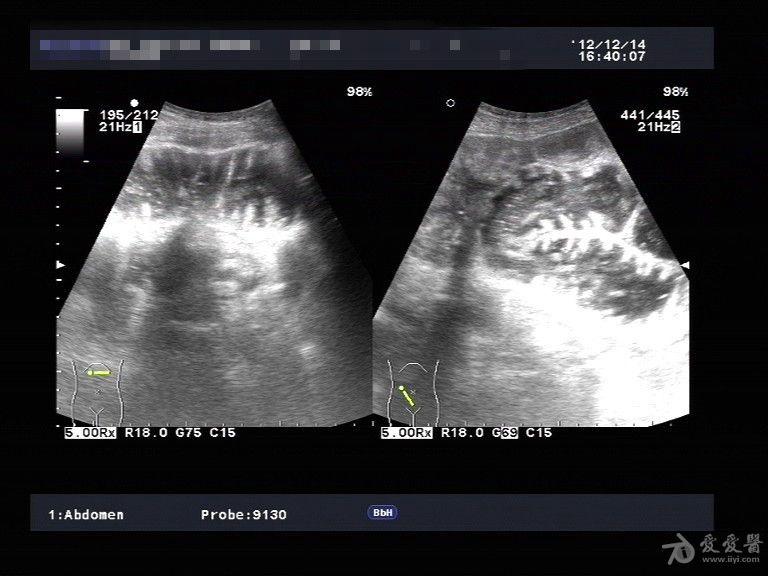

大家看看可以报肠梗阻吗?

图片尺寸515x506